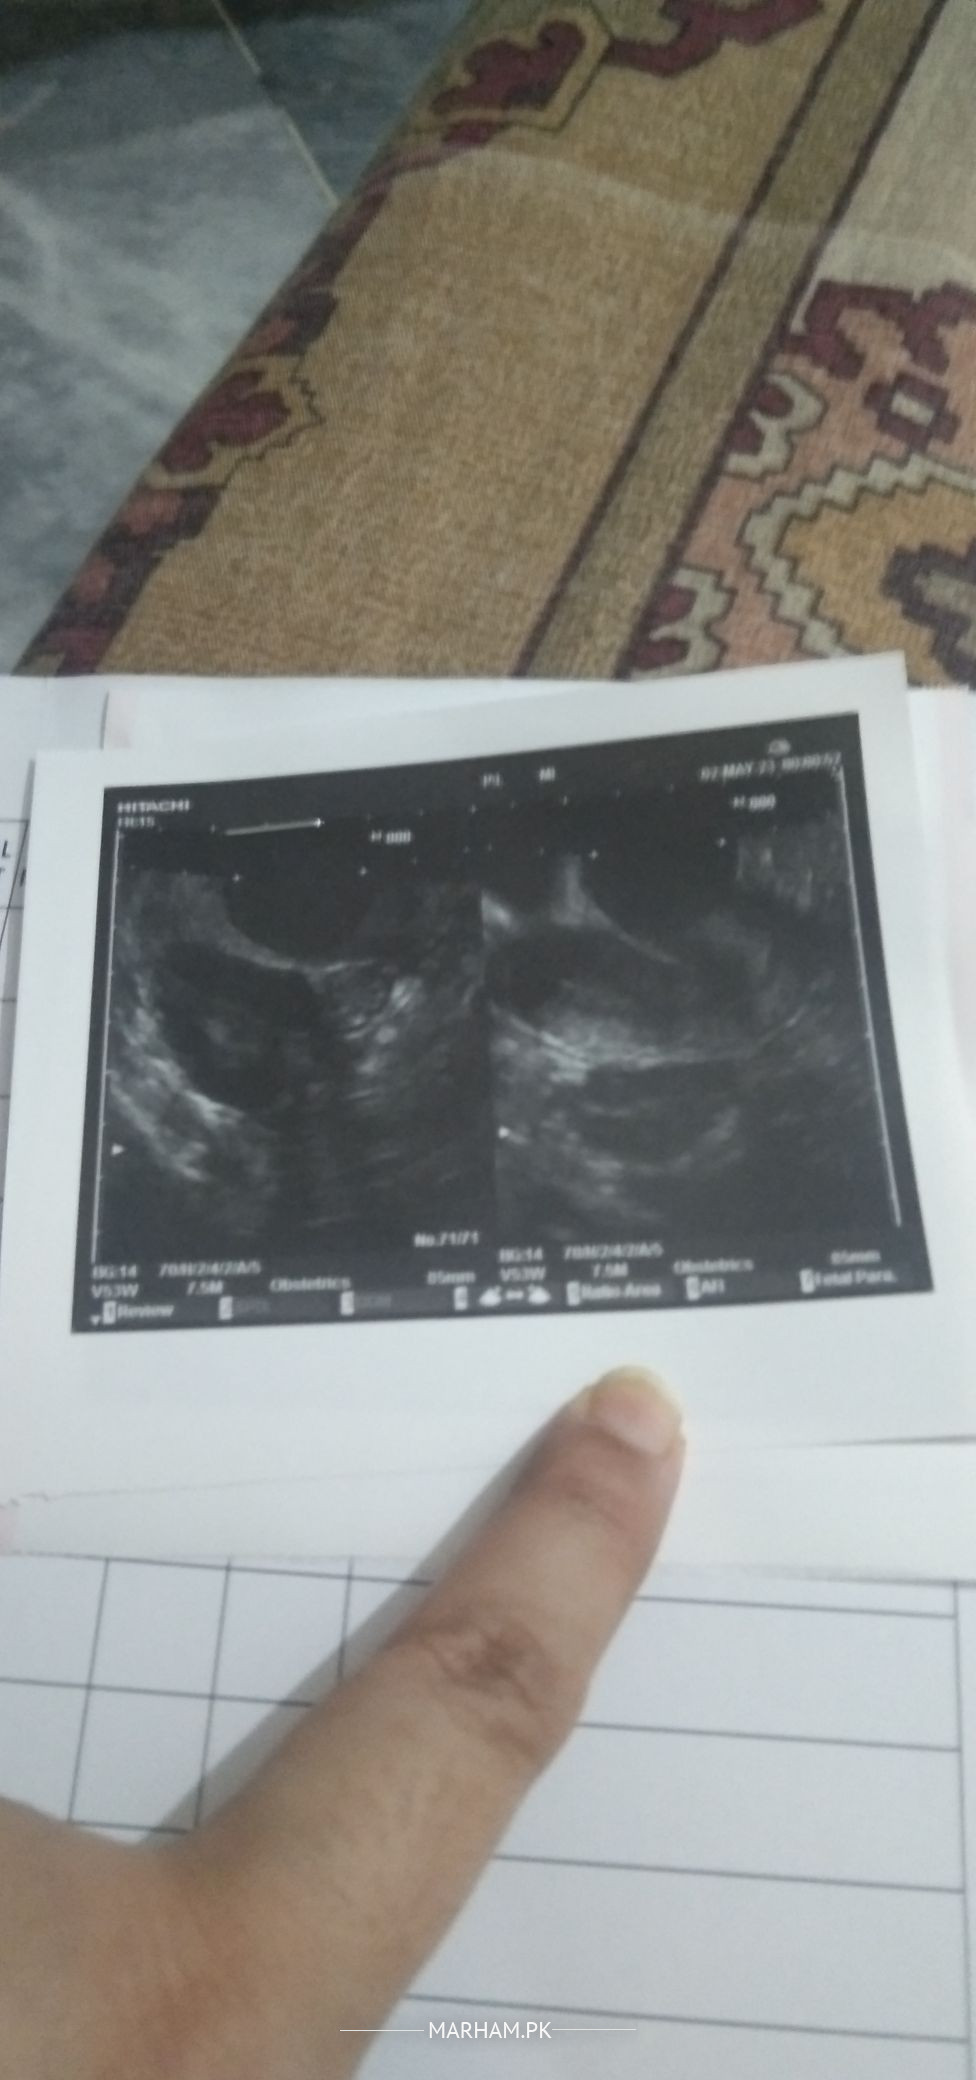

for injection u have to do ultrasound at day 12 of menses for follicle size

g doctor ny date Scan ki btai ha

Attach Photo here: